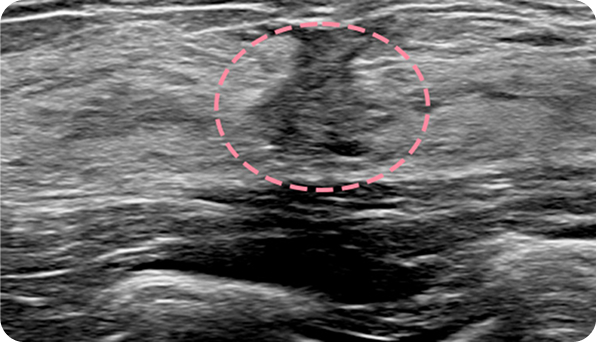

양성 종양은 여러 개가 동시에 생겨나기도 합니다. 정상적인 유방 조직 보전에 신경 쓰며 맘모톰 시술을 섬세히 진행했고, 6개월 뒤 추적 관찰을 위한 유방초음파에서 종양이 깨끗이 제거된 것을 확인 했습니다. 일부 반흔 조직은 자연스럽게 호전될 것으로 보여 좋은 예후가 기대되었습니다.